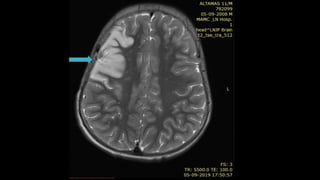

SUPERFICIAL CEREBRALVEIN

THROMBOSIS

SuperficialThrombosis With DST SuperficialThrombosis Without

DST

• Rare (5% of all CVTs)

• May cause convexal

subarachnoid hemorrhage

• May see "cord" sign on CT which

is called hyperintense vein sign on

MR representing adj thrombosed

vein

•T2* (GRE, SWI) key to diagnosis

○ "Blooming" thrombus in vein(s)

SWI showing blooming

in

superficial cortical

veins

in right VOT

T1WI

showing

linear

hyperintensi

ty

• #146 This is a c/o VOT thrombosis.Axial T1wi Mri BRAIN shows T1 hyperintensity in post central gyrus , typical site for VOT s/o thrombosis and SWI shows blooming in the region of thrombosed vdein

• #147 Saggital view MR venography image shows non visualization of vein of tolard

• #148 Case of young women presented with seizure and altered mental status .T1 wi shows sublte “ dot sign” of T1 hyperintensity within a small cortical vein , within expected location of vein of labbe. T2 hyperintense area of mass effect involving left temporal lobe grey and white matter